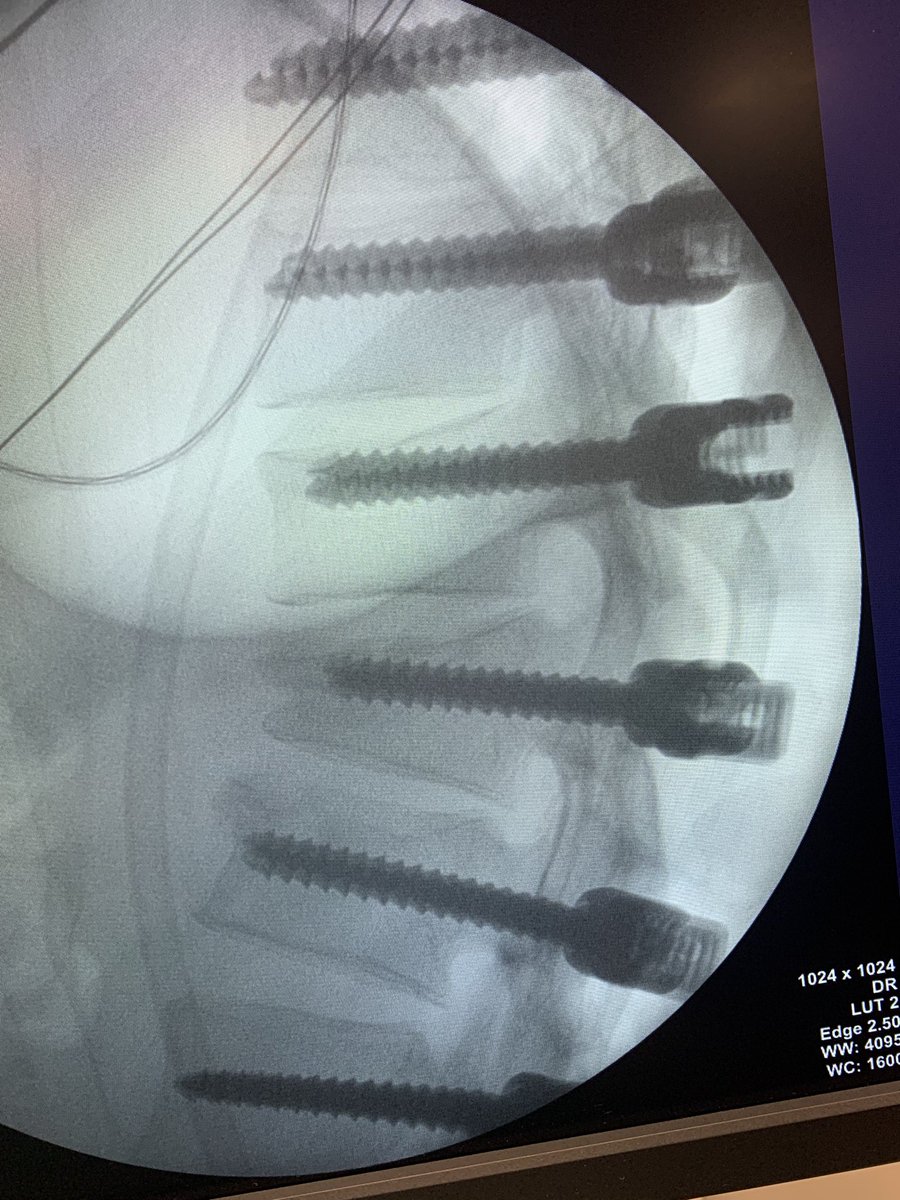

Male 40yo, healthy and physically active.

How do you treat this fracture?

Nonop, ORIF with plate or nailing?

@InvictaOrtho @traumaticum @rkh_md @Gnomelover1970 @aqueipot @DrMarecek

@DrBhavinJadav

#orthotwitter